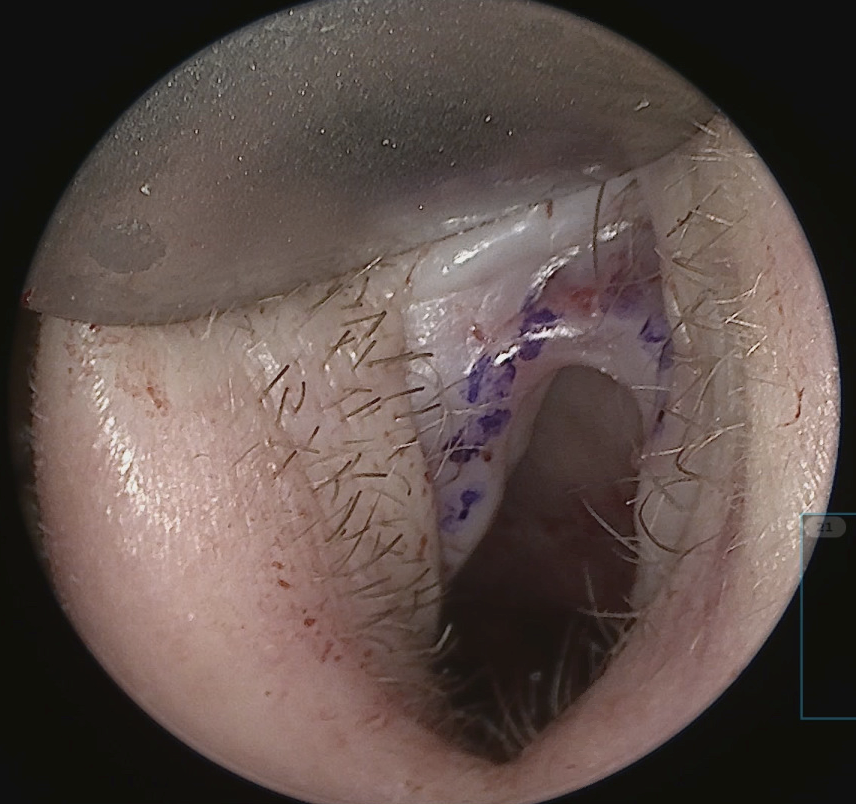

The intercartilaginous incision is made with a 15 blade beginning laterally and carried medially, taking care to stay caudal to the vestibular arch to reduce the risk of post-operative vestibular stenosis (figure 1). The incision is continued onto the anterior aspect of the caudal septum. While making the incision, a converse retractor in the non-dominant hand is used to evert and tense the tissue. The blade and converse retractor move in a synchronized fashion while progressing from lateral to medial to allow for optimal exposure and tension/counter-tension for a precise incision.

Though harvesting of the cartilage comes from within the conchal bowl, the incision is placed laterally on the peak of the antihelix (Figure 6). This prevents post-operative webbing and cicatricial scaring. Additionally, the scar hides nicely on the natural peak of the antihelix. The conchal bowl and corresponding posterior auricle are injected with a 50:50 mixture of 1% lidocaine with 1:100,000 and 0.25% bupivacaine with 1:200,000 epinephrine. The incision is made with a 15 blade to the cartilage. A freer or tenotomy scissor is used to establish the subperiosteal plane. The conchal skin is elevated off the cartilage dissecting medially. Soft tissue elevation is the performed on the posterior surface of the cartilage. The graft, measuring approximately 10 mm x 25-30 mm, is sharply excised from the conchal cartilage with a 15 blade and placed in a saline bath. Hemostasis is obtained in the wound bed, and the incision is closed with a 5-0 fast absorbing gut suture in a running fashion. A bolster is placed to eliminate dead space and prevent a post-operative hematoma. A 5” x 9” occlusive petroleum gauze is rolled and placed snuggly in the conchal bowl. A 3-0 Nylon suture is placed transmurally through the conchal bowl with a non-adherent gauze on the posterior auricle to protect the skin. Bacitracin ointment is applied to the incision and bolster.